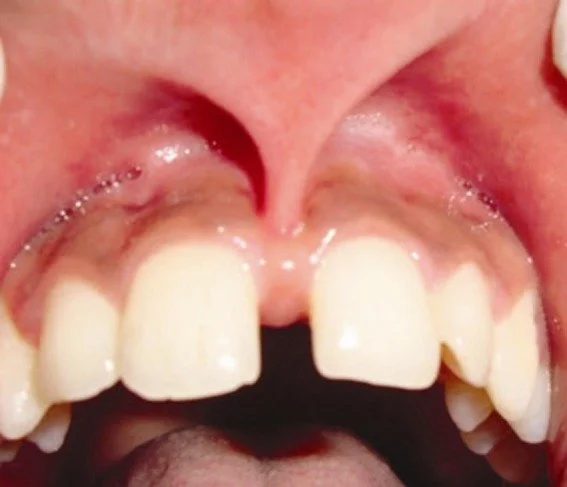

When the frena attaching the upper or lower lips are papillary penetrating, they are problematic because lip movements can tug on the papilla harshly, resulting in a few different problems:

2. The frenum can exert lateral pressure that can spread the teeth apart-usually the middle two incisors. If orthodontics is performed to close the space, it will reopen if the frenum is not corrected.